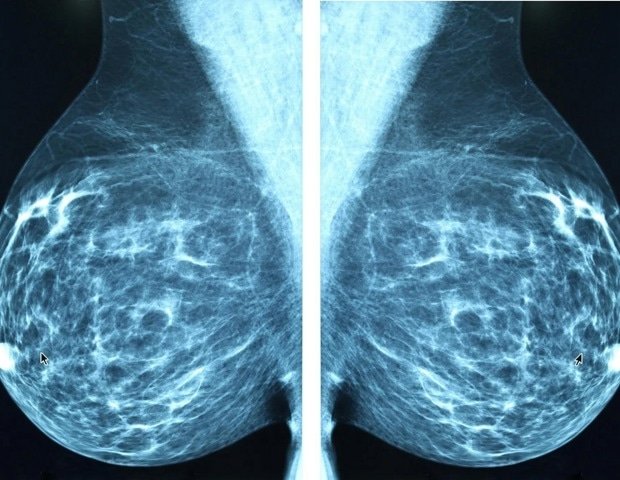

A new study published today in Science Translational Medicine by researchers at the University of Texas MD Anderson Cancer Center, details a therapeutic vulnerability in patients with an aggressive subtype of triple-negative breast cancer.

Led by Khandan Keyomarsi, Ph.D., professor of Experimental Radiation Oncology, the study shows that simultaneous inhibition of ATR and PKMYT1 triggers a type of cell death in Rb1-deficient breast cancer models.

Using genomic profiling, proteomics, and patient-derived xenografts, the researchers found that loss of Rb1—a gene important for normal cell division—disrupts DNA repair processes and forces cancer cells to rely on ATR- and PKMYT1-dependent survival pathways, creating a vulnerability that can be selectively targeted.